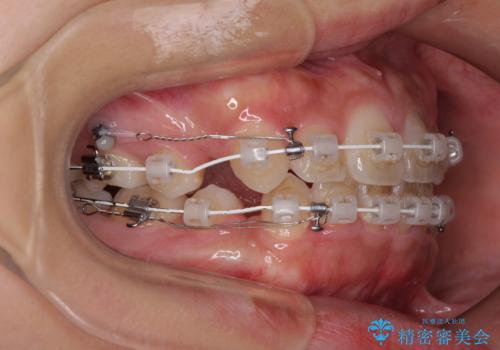

- 審美装置

- 前歯のデコボコと口元の突出感を気にして来院された患者様です。

上下左右第一小臼歯4本を抜歯し、ワイヤー装置にて口元を引っ込めるよう矯正治療を行うこととしました。

非常にスムーズに歯列移動が行われ、当初は2-2.5年を予想していましたが、僅か1年4ヶ月で治療を終えることができました。